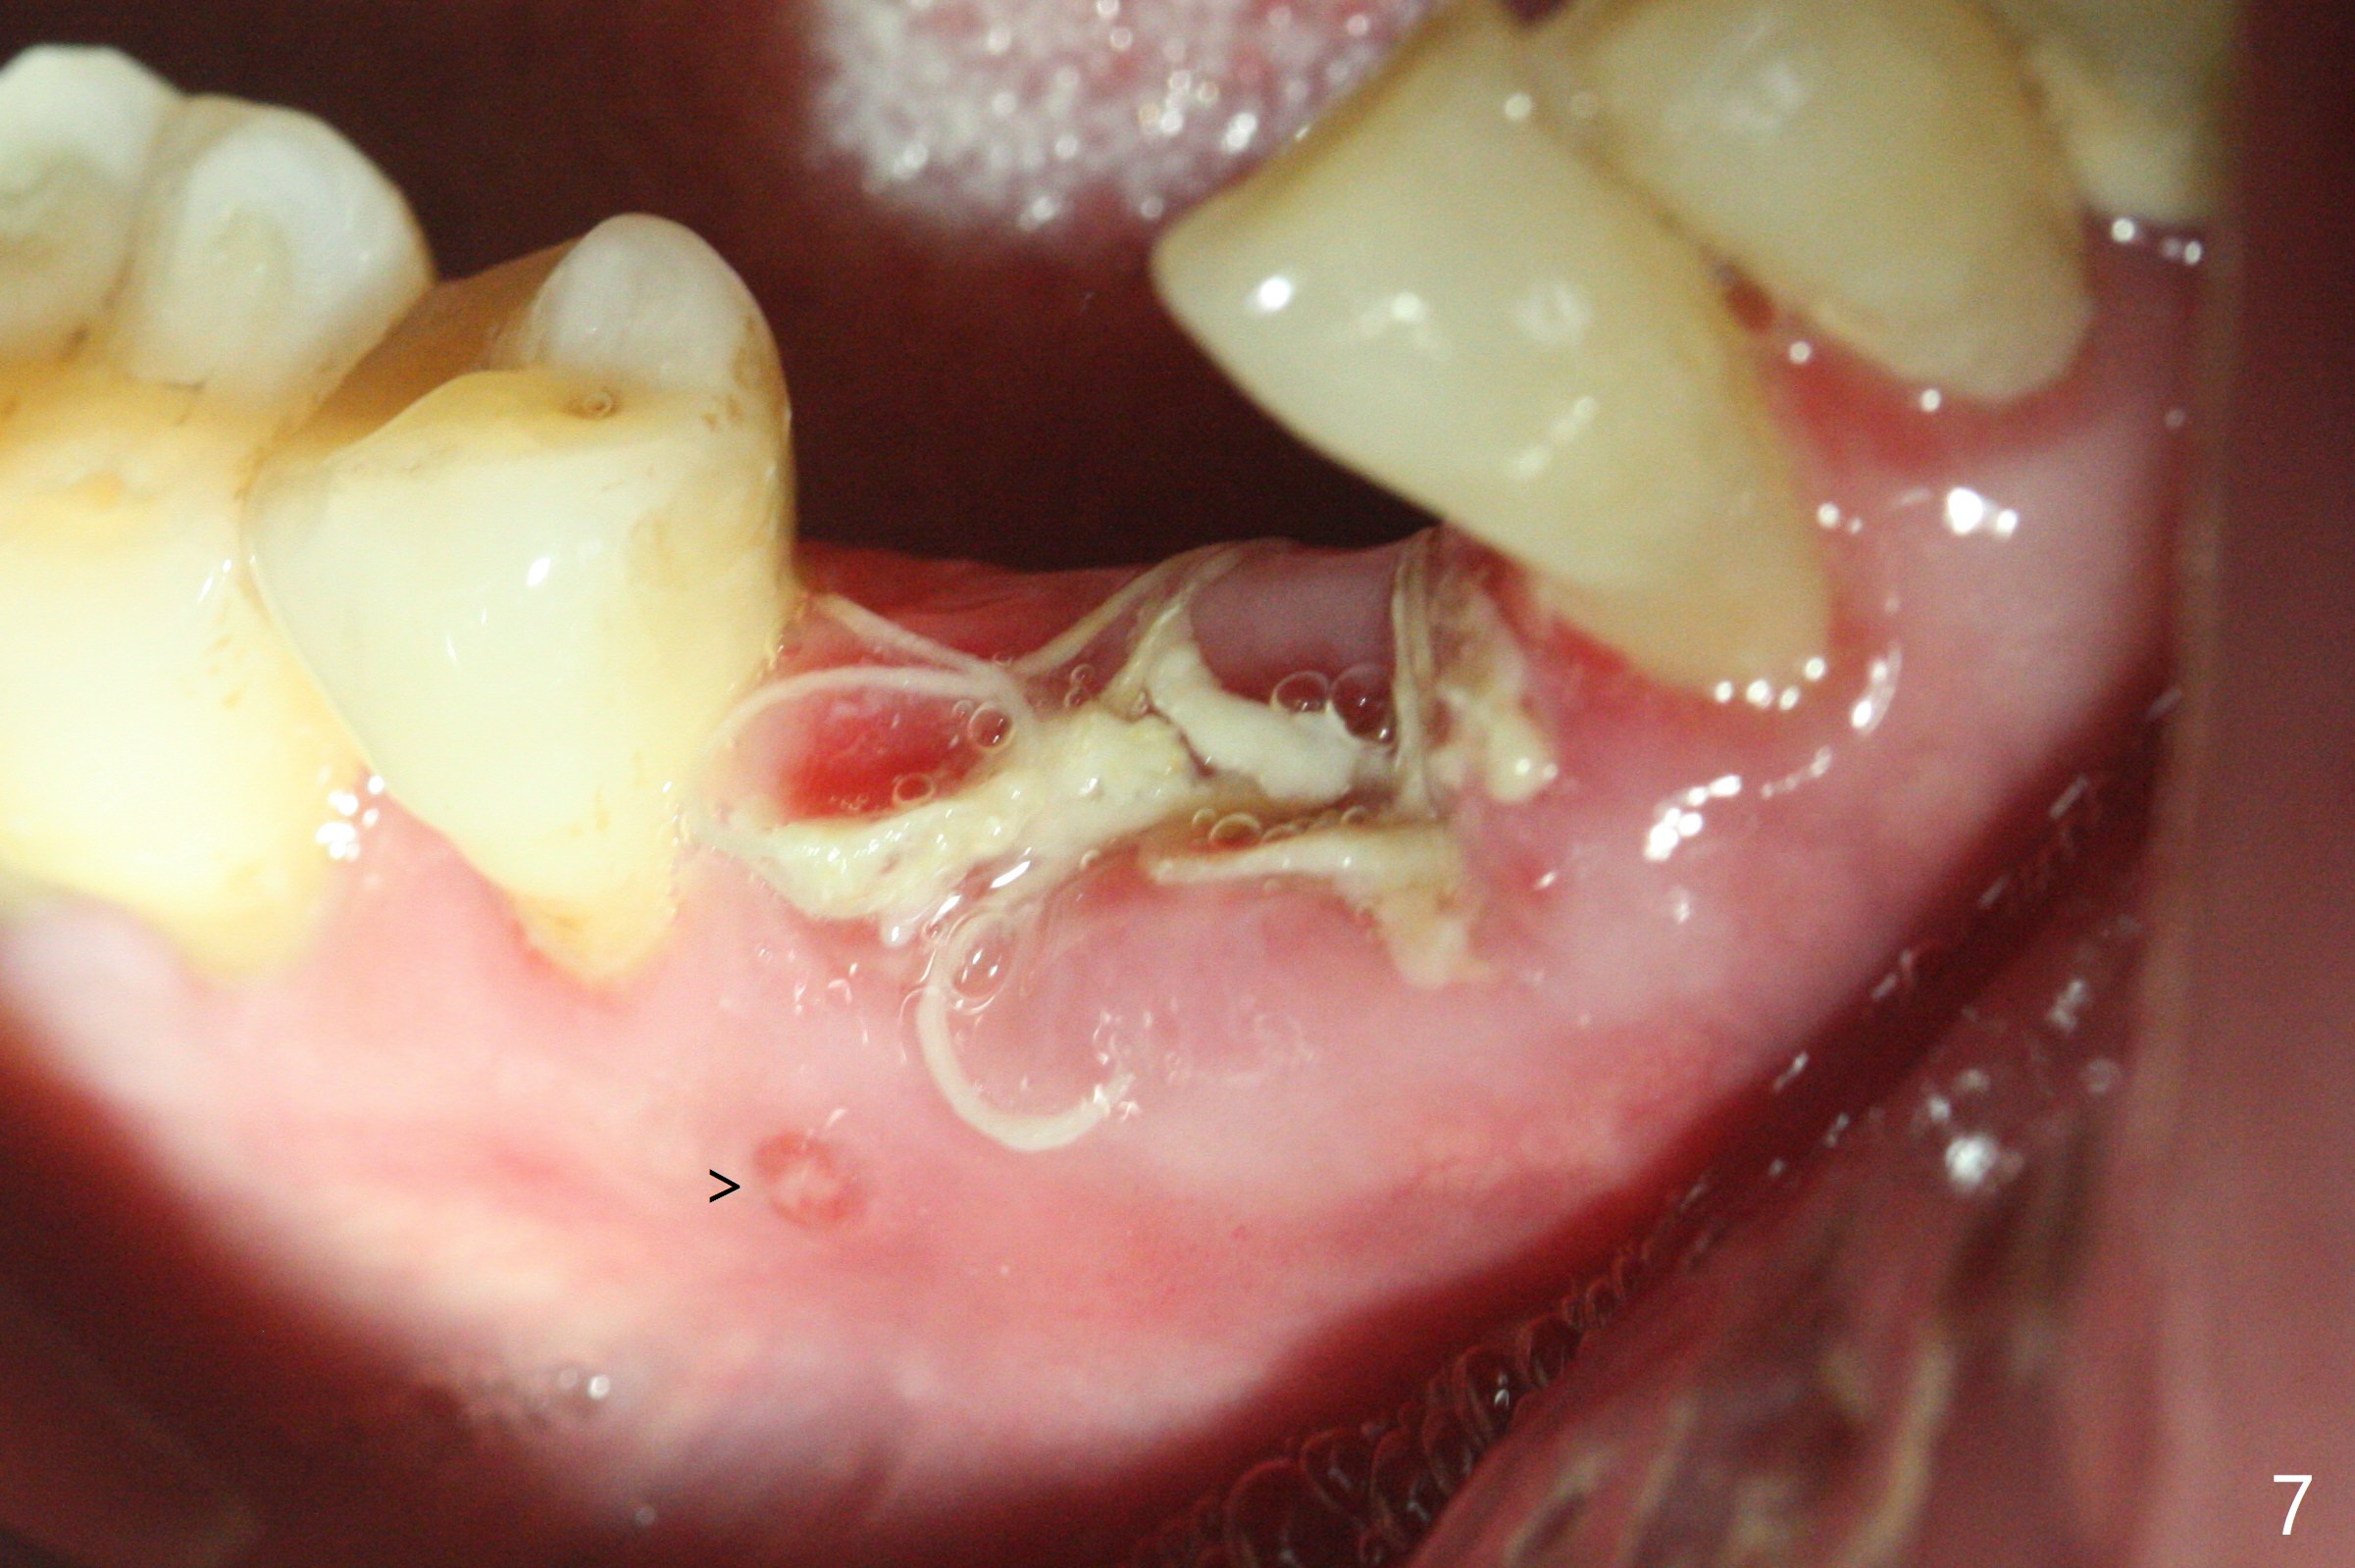

Since the distal crest is low at #19 after extraction (Fig.3), a 4.5x11 mm FC implant (Fig.4 green) will be immediately placed in the mesial socket (lingual), which has more clearance from the Inferior Alveolar Canal (yellow). Sticky bone will be initially up to the implant plateau, followed by insertion of a cemented abutment (pink), placement of the 2nd round of bone graft (red) and fabrication of an immediate provisional (white). To save time, a piece of collagen plug is inserted into the apical portion of the distal socket (blue). The distal crest will be expected to increase ~ 3 mm by the procedure mentioned above. The #32 socket heals with apparent exposure of collagen plug 2 weeks postop (Fig.5). The #27 and 28 sockets heal with fresh granulation tissue 2 weeks postop (Fig.6). The fistula buccal to #28 socket appears to have shrunken 2 weeks postop (Fig.7).